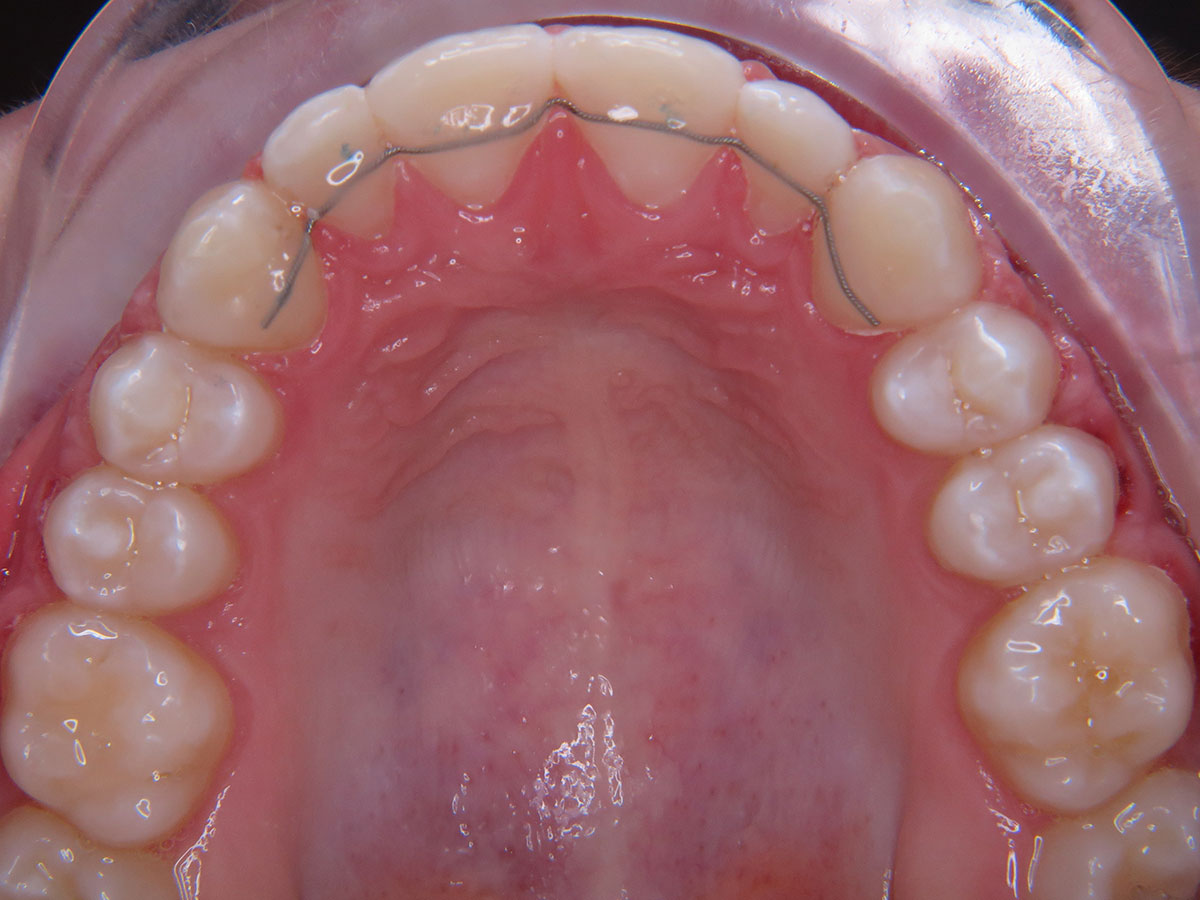

Um das Ergebnis dauerhaft zu sichern, einem Rückfall vorzubeugen und auch weiteren unerwünschten Zahnbewegungen entgegenzuwirken, kommen Stabilisierungsgeräte zur Anwendung. Diese gibt es als herausnehmbare Nachtspangen (Platten oder transparente Schienen) und in Form festsitzender Drähte, sogenannte „Retainer", die auf die Innenseite der Frontzähne geklebt werden.

Die Langzeitstabilisierung mit einem Retainer bietet den zuverlässigsten Schutz vor Rückfällen und alterstypischen Veränderungen der Frontzahnstellung. Im Laufe der Tragezeit können jedoch die Klebeverbindung am Bogen oder der Draht selbst sich lösen oder brechen. Um den Behandlungserfolg nicht zu gefährden, sollte in einem solchen Fall eine sofortige Reparatur oder Erneuerung des Retainers erfolgen.